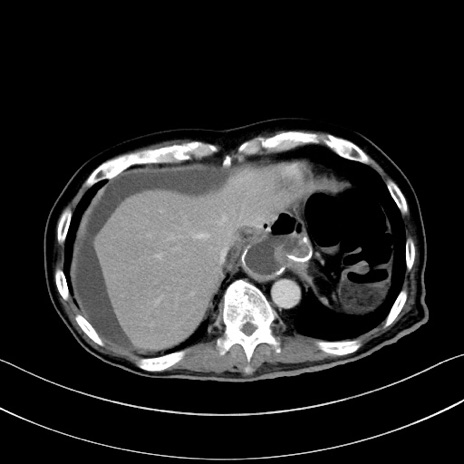

冠状断像

【症例】60歳代男性

【主訴】嘔吐

【現病歴】胃癌にて胃全摘後。食思不振が悪化し、夜中に嘔吐することがある。

【既往歴】胃癌、胃全摘、脾摘、胆摘後

【データ】WBC 5900、CRP 10.56